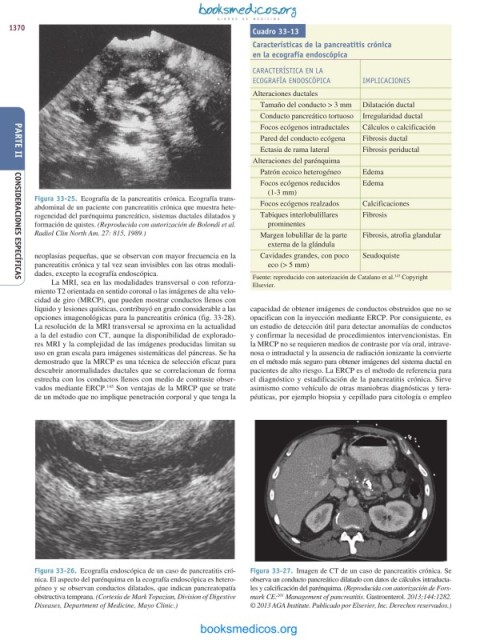

1370 Cuadro 33-13

Características de la pancreatitis crónica

en la ecografía endoscópica

CARACTERíSTICA EN lA

ECoGRAFíA ENDoSCÓPICA ImPlICACIoNES

Alteraciones ductales

Tamaño del conducto > 3 mm Dilatación ductal

Conducto pancreático tortuoso Irregularidad ductal

Focos ecógenos intraductales Cálculos o calcificación

Pared del conducto ecógena Fibrosis ductal

Ectasia de rama lateral Fibrosis periductal

Alteraciones del parénquima

Patrón ecoico heterogéneo Edema

Focos ecógenos reducidos Edema

(1-3 mm)

abdominal de un paciente con pancreatitis crónica que muestra hete- Focos ecógenos realzados Calcificaciones

rogeneidad del parénquima pancreático, sistemas ductales dilatados y Tabiques interlobulillares Fibrosis

Radiol Clin North Am. 27: 815, 1989.) Margen lobulillar de la parte Fibrosis, atrofia glandular

externa de la glándula

neoplasias pequeñas, que se observan con mayor frecuencia en la Cavidades grandes, con poco Seudoquiste

pancreatitis crónica y tal vez sean invisibles con las otras modali- eco (> 5 mm)

dades, excepto la ecografía endoscópica. Fuente: reproducido con autorización de Catalano et al. Copyright